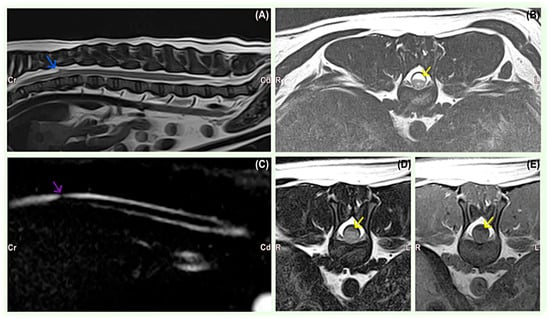

MRI findings consisted of the teardrop-shaped widening of the dorsal subarachnoid space at the site of the SAD, associated with the compression of the spinal cord in all dogs (Table 2). The lesions were hyperintense on T2-weighted sequences (Figure 1) and iso- or hypointense on T1-weighted images in all cases. FLAIR images showed lesion suppression in seven cases, indicative of CSF accumulation. The sagittal FASE image showed the abrupt attenuation of the affected subarachnoid space and apparent cranial or caudal dilatation of the contiguous subarachnoid space consistent with SAD in all cases. There was no gadolinium enhancement on T1-weighted post-contrast sequences in any MRI studies. SAD was located in the thoracic and thoracolumbar regions from the T7 to L1 level in nine small breed dogs. A large breed dog, Rottweiler, was diagnosed with a C2–C3 SAD lesion. T13–L1 was the most affected site (3/10), followed by T10–T11 (2/10), T12–T13 (2/10), T9–T10 (1/10), T7 (1/10), and C2–C3 (1/10).

Figure 1. French Bulldog, 0Y8M, male. (A) Sagittal T2-weighted image of the thoracolumbar spine showing dilatation of the dorsal subarachnoid space at the level of T10 and T11 (arrow) and the narrowing of the subarachnoid space at the level of the cranial endplate of T12, suggesting leptomeningeal adhesions. (B) Transverse T2-weighted image of the spine at the level of T11–T12 showing dilatation of the dorsal subarachnoid space at the level of T10 and T11 (arrow) and a faint increase in the signal intensity of the spinal cord. (C) The FASE sequence showed abrupt attenuation in the continuity of the affected aspect of the subarachnoid space (arrow) and apparent dilatation of the subarachnoid space consistent with an arachnoid diverticulum. (D) The transverse FLAIR sequence suppressed the lesion, suggesting CSF (arrow). (E) Transverse post-contrast T1-weighted image showing no abnormal enhancement identified. The arrow indicates hypointense subarachnoid fluid dilation.